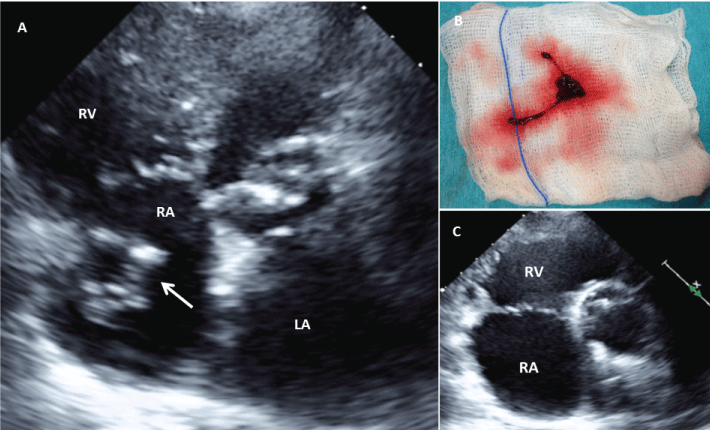

A 83 years-old woman underwent percutaneous balloon mitral valvuloplasty (PBMV) due to symptomatic rheumatic mitral stenosis. The transesophageal echocardiogram before PBMV revealed no atrial thrombus. PMBV was performed under fluoroscopic guidance. Following PBMV, an obstruction of the catheter lumen was detected. The transthoracic echocardiogram (TTE) showed a giant mass in the right atrium (Figure 1A), free mobile and eventually prolapsing into the right ventricle (Video). The large thrombus was completely removed percutaneously (Figure 1B), confirmed by TTE (Figure 1C). Despite the use of unfractionated heparin, thrombus formation during PBMV can occur. Echocardiographic imaging is crucial for the detection of thrombus, which cannot be identified by fluoroscopy.

Figure 1: A) Transthoracic Echocardiography (TTE) showing the large mass/thrombus floating in the right atrium (arrow);

B) Fresh thrombus removed using transcatheter aspiration technique.

C) TTE showing no evidence of residual thrombus in the right atrium. RA: Right atrium, LA: left atrium, RV: right ventricle.